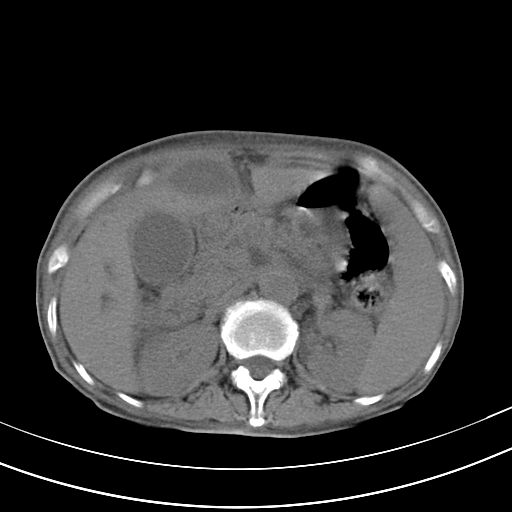

病人上腹部胀痛拌全身黄染八天

右侧少量胸水,胆囊增大,肝内胆管扩张,肝门部结构杂乱,建议增强。

肝内胆管及胰管扩张考虑为胰头区占位,肝门淋巴结增多,肝内多发低密度影,考虑为转移。门脉高压,脾大,胆囊大。

肝内胆管及胰管扩张,胰头增大考虑为胰头区占位,肝门淋巴结增多,考虑为转移。建议增强,脾大,胆囊大,壁厚,慢性胆囊炎。胃壁好像也增厚,且有一肿物。

胆囊增大,肝管扩张

脾大,

腹水,右胸腔少量积液。

胰腺炎。

1)考虑胰头癌并胆系低位梗阻;建议行ct增强扫描检查。2)慢性胆囊炎。3)脾大。4)少量腹水。5)双侧少量胸腔积液。